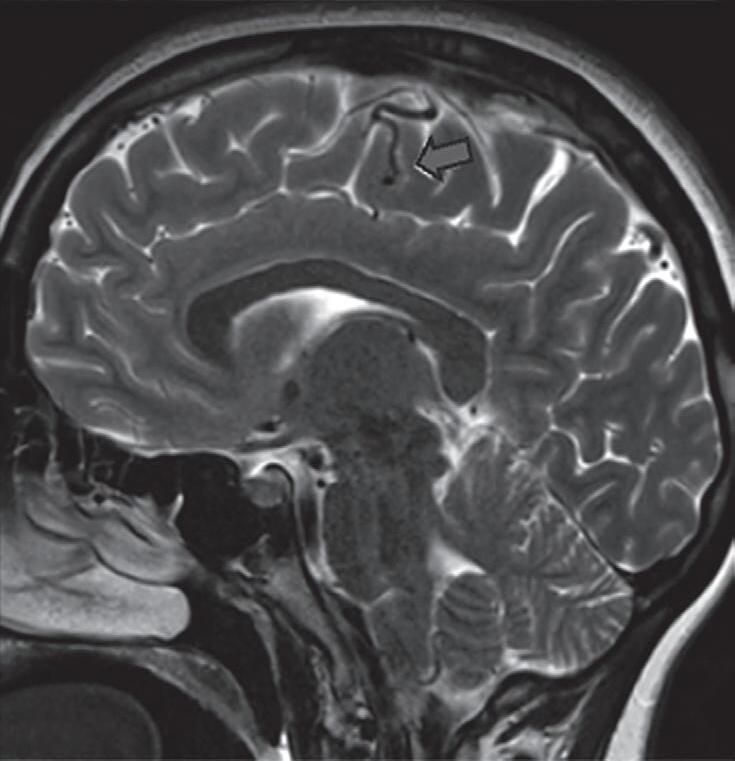

A suspeita diagnóstica das MAVs geralmente é feita por meio de métodos não invasivos de aquisição de imagem, tais como tomografia computadorizada (TC), angiotomografia, ressonância magnética (RNM) e angiorressonância, contudo, as informações anatômicas vasculares necessárias para o planejamento e a execução terapêutica demandam geralmente do estudo dinâmico da angioarquitetura da MAV pela arteriografia cerebral, considerado o exame padrão-ouro para o diagnóstico (Figs. 1-21 e 1-22).35

é geralmente o primeiro exame realizado na investigação diagnóstica. Algumas alterações presentes nessa tomografia, associadas à história clínica do paciente podem direcionar a suspeição diagnóstica; são eles: pacientes jovens com hemorragia intraparenquimatosa lobar espontânea, sangramento inexplicável intraventricular ou subaracnóideo, presença de calcificações curvilíneas ou salpicadas, ou imagens serpiginosas espontaneamente hiperdensas, que podem corresponder a vasos anômalos integrantes do nidus, a veias de drenagem ou a artérias nutridoras dilatadas. Embora a angiotomografia possibilite uma melhor visualização das estruturas vasculares, a ressonância magnética em contrapartida, permite melhor

Fig. 1-21. TC de crânio sem contraste em cortes (a) axial e (b) coronal. (c) RNM encéfalo T1 com contraste axial. (d) Angiorressonância arterial sagital. Arteriografia digital em (e) AP e (f) perfil, demonstrando MAV não rota localizada no giro pré-central à esquerda nutrida por ramos da artéria cerebral média e caloso marginal esquerdo. Setas azuis apontando para o nidus da MAV.

visualização da anatomia cerebral, das alterações parenquimatosas, bem como: gliose peri ou intranidal, atrofia parenquimatosa com dilatação focal do sistema ventricular, possibilita a diferenciação da hemorragia aguda da crônica (visualização da hemossiderina nas sequências gradiente eco [GRE] e hidrocefalia (secundária a hemorragia prévia e ou compressão do sistema ventricular por veias de drenagem dilatadas).35